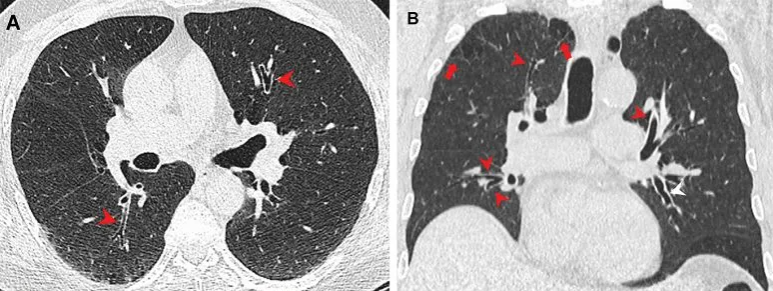

Plicní emfyzém u (A, B) marihuany a (C, D) kuřáků tabáku. (A) Axiální a (B) koronální CT snímky u 44letého muže kuřáka marihuany ukazují paraseptální emfyzém (šipky) v bilaterálních horních lalocích. (C) Axiální a (D) koronální CT snímky u 66leté kuřačky tabáku s centrilobulárním emfyzémem reprezentovaným oblastmi centrilobulární lucence (šipky). Kredit: Radiologická společnost Severní Ameriky